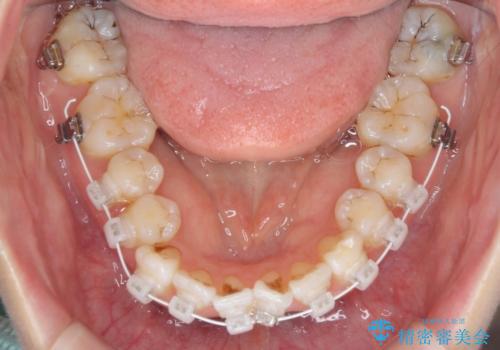

- 審美装置

右上4番目の歯を抜歯し、上顎裏側に補助装置を装着して左の歯列全体を後方に移動させながら、正中を合わせるようにして行くこととしました。